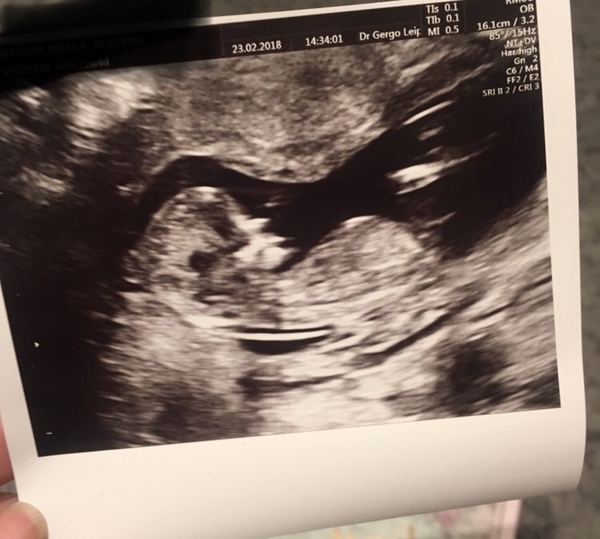

Nixen · 01/03/2018 18:33

@Fia we’ve been told (via Harmony) we are having a girl and I’ve just gone to check... and there is a light on her belly!

@Fia256 has mine got a light or is it just the photo?

Had to go quickly edit to remove my details and share - see the light on her belly! You might be on to something @Fia!

Ooh I've just looked at DD's scam pic and there's a light. Have you found the new way to predict the sex Grin

Mona yes yours looks like it's got a really big light on the tummy!

Nixen how exciting! That's one so far definitely proven right then 😜